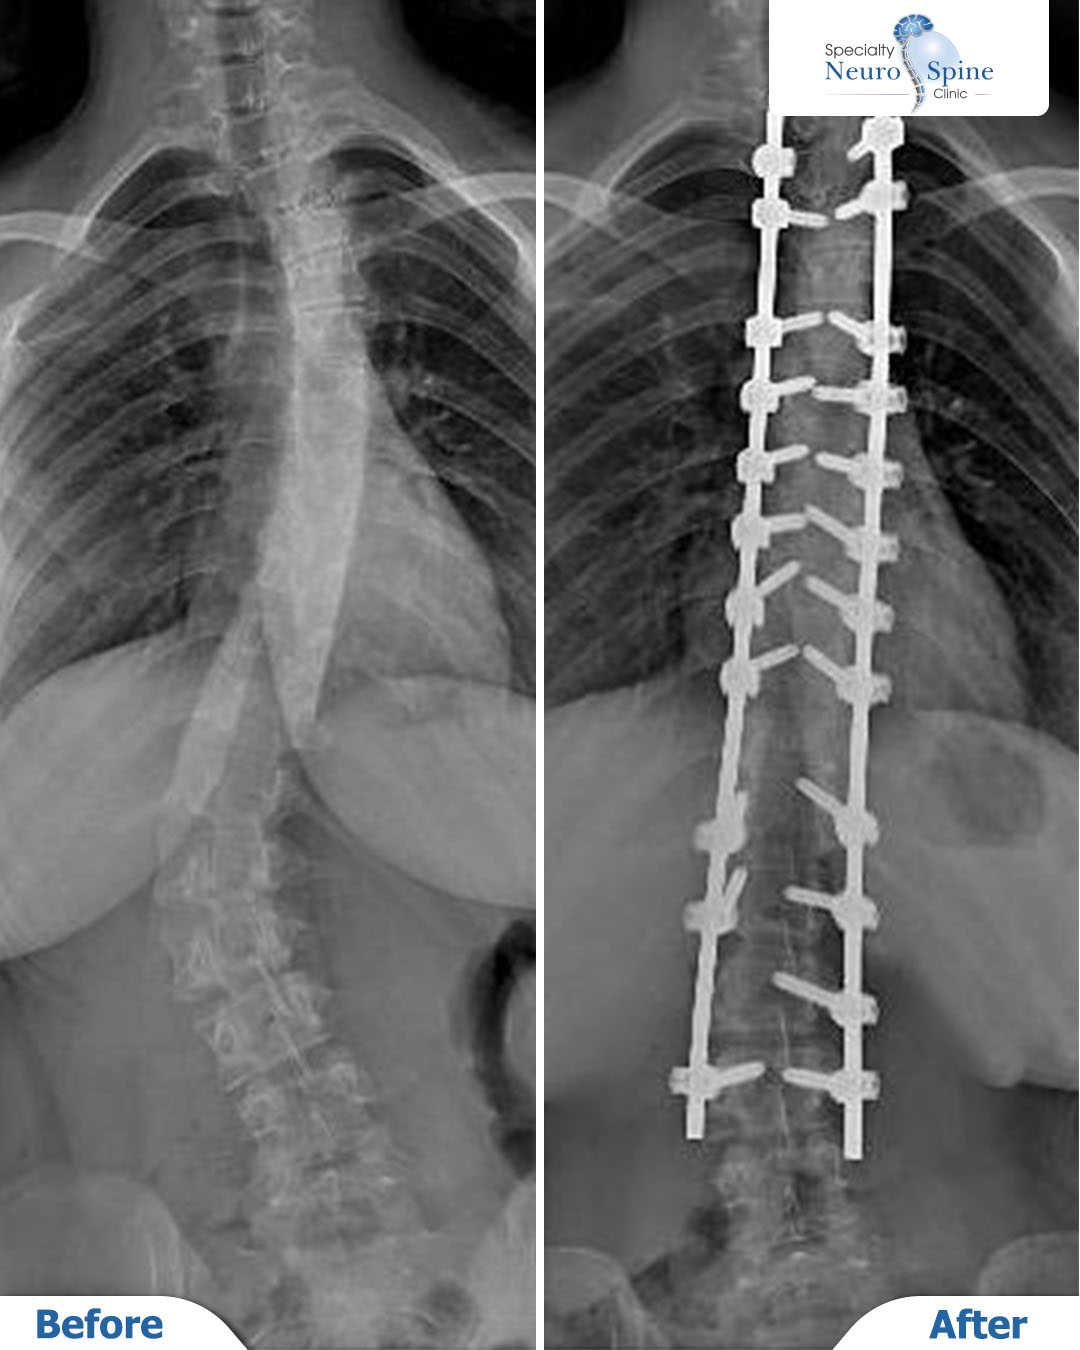

Before-and-after X-rays of our dear patient Tayba, a 16 years old from Iraq, who underwent spinal curvature correction surgery from the second thoracic vertebra (T2) to the fourth lumbar vertebra (L4), using advanced minimally invasive endoscopic techniques.